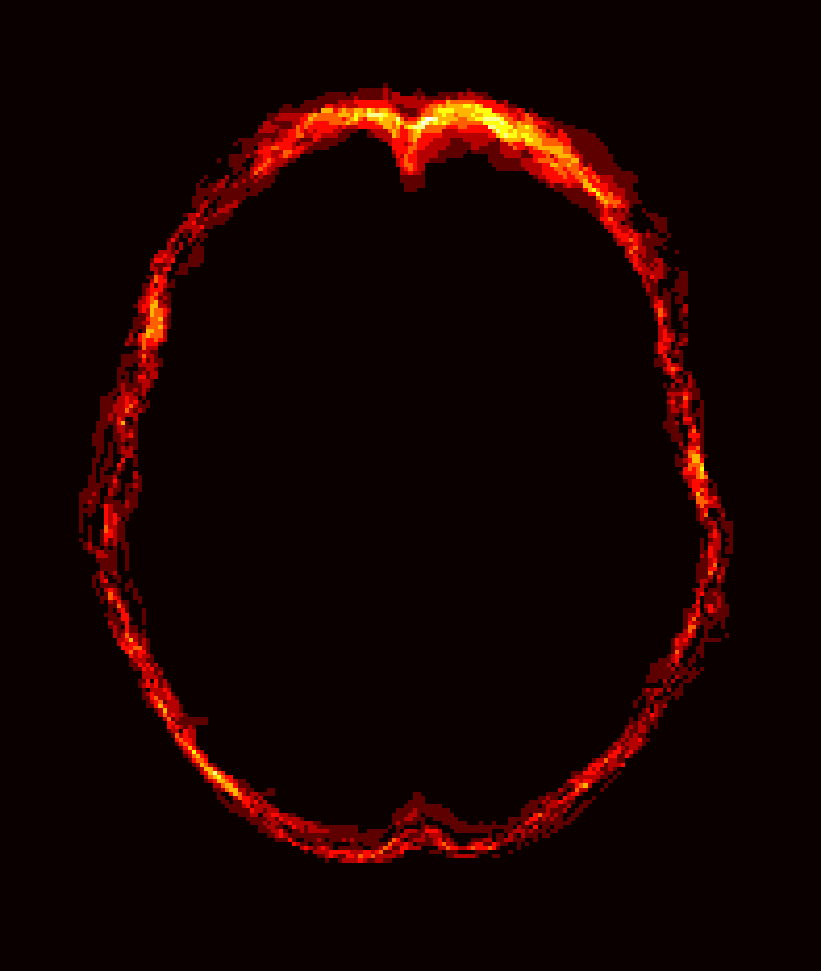

Fig. 1 shows example images from each dataset to illustrate image variability. IBSR and LPBA40 contain images from normal subjects and include large portions of the neck; BRATS has very low out-of-plane resolution; and the TBI dataset contains large pathologies and abnormal skulls.

Refer to caption

Figure 1: Illustration of image appearance variability on a selection of images from each (evaluation) database. From top to bottom: IBSR, LPBA40, BRATS and TBI.